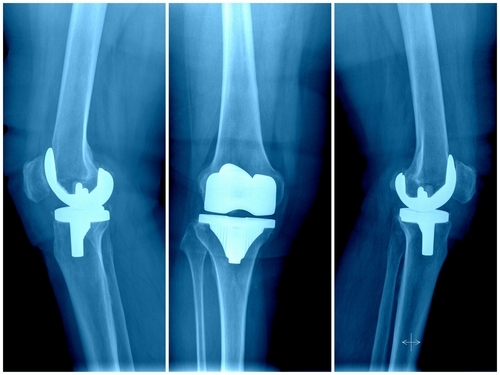

As the government capped price for knee implants to make it affordable, orthopaedic surgeons on Thursday called the measure a boon for the poor people, but urged the government to ensure that the quality of implants do not come down along with price.

The NPPA on Wednesday fixed the price for primary knee replacement of titanium alloy at Rs 38,740 while the price for revision knee replacement of any material was pegged at Rs 62,770. The price for Hi-Flex primary knee replacement was fixed at Rs 25,860 and that of cobalt chromium alloy at Rs 24,090.Ishwar Bohra, Senior Consultant, Joint Replacement & Arthroscopy Surgeon at BLK Super Speciality Hospital, termed the move a people-friendly effort, which will allow more patients of knee problems to opt for the surgeries, which they may have avoided till now due to the high cost.He however noted that the quality for revision knee replacement surgeries may get affected as prices for this procedure, which is more complex requiring the surgeon to remove the original implant which would have grown into the existing bone, cannot be fixed as different systems and parts may be required which cannot be predicted before the surgery.